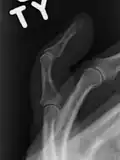

- X-ray showing fracture at the insertion of the extensor tendon